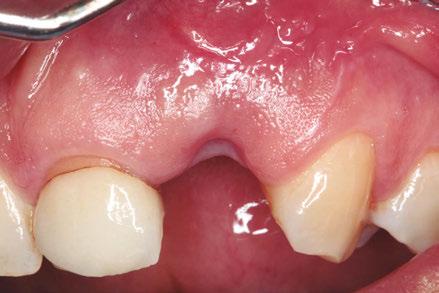

–Implante inmediato en incisivo lateral superior con técnica de «Socket Shield» y acceso vestibular para legrado de la lesión periapical, por el Dr. Ignacio Tormo Jiménez y cols. [106]